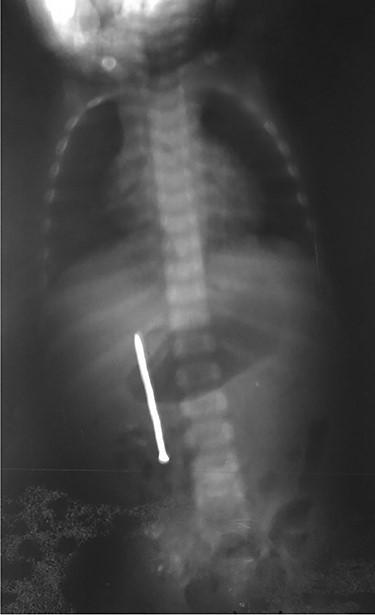

Abdominal examination was normal. A repeat abdominal radiography was done. The nail’s position had not changed from the first X-ray site, with no free peritoneal air (Fig. 2).

Plain radiography plays the main role both in the diagnosis and the choice of operative interventional moment—either by pinpointing the radio-opaque image, or by showing certain FB characteristics, or by noting images suggesting complications (absent in our case), or even by projecting the FB in the same place over a period of time, an aspect inductive of fistula. In our case, right-edge superposition of the FB image upon the lumbar spine is characteristic of FB positioning in the second part of duodenum [5, 6]. Its persistence in the same place (the second part of the duodenum as in our case) suggests the presence of a duodenal fistula or perforation, which requires surgical intervention [7].